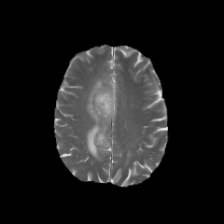

We also qualitatively explored the zero-shot chain-of-thought (CoT) capability of Med-PaLM M on the MC TB dataset. In contrast to the classification setup, we prompted the model with a text-only exemplar to generate a report describing the findings in a given image in addition to a yes/no classification prediction. In Figure 3, we present qualitative examples of zero-shot CoT reasoning from the Med-PaLM M 84B and 562B variants. In particular, both Med-PaLM M variants were able to identify the major TB related lesion in the correct location. However, according to expert radiologist review, there are still some omissions of findings and errors in the model generated report, suggesting room for improvement. It is noteworthy that Med-PaLM M 12B failed to generate a coherent visually conditioned response, which indicates that scaling of the language model plays a key role in the zero-shot CoT multimodal reasoning capability (i.e. this might be an emergent capability [13]).

In Figure 6, we illustrate a qualitative example of chest X-ray reports generated by Med-PaLM M across three model sizes along with the target reference report. For this example, our panel of radiologists judged the Med-PaLM M 12B report to have two clinically significant errors and one omission, the Med-PaLM M 84B report to have zero errors and zero omissions, and the Med-PaLM M 562B report to have one clinically insignificant errors and no omissions.